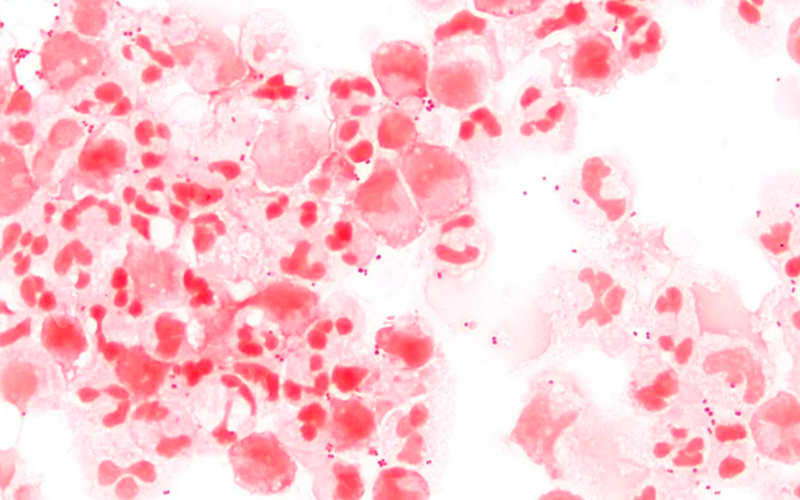

Neisseria meningitidis, a bactéria que causa a meningite meningocócica. — Foto: Wikimedia/Divulgação